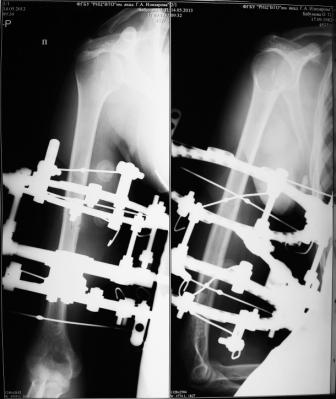

После остеосинтеза